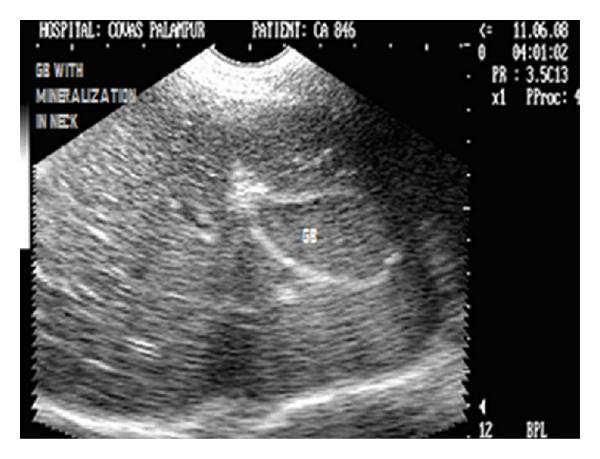

Hepatic disease is often treatable and has a predictable prognosis when a definitive diagnosis is made. The aim of clinicopathological evaluation of hepatobiliary affections is to identify and characterize hepatic damage and dysfunction, identify possible primary causes of secondary liver disease, differentiate causes of icterus, evaluate potential anaesthetic risks, assess prognosis and response to xenobiotics, and monitor response to therapy. This paper describes the different diagnostic methods and imaging techniques employed in diagnosis of hepatobiliary affections in dogs. Besides reviewing the significant clinical manifestations and imaging structural abnormalities in diagnostic approach to different hepatic affections, it also depicts radiographic, ultrasonographic, and wherever applicable, the laparoscopic characterization of different hepatic affections and target lesions encountered in clinical cases presented in the Teaching Veterinary Clinical Complex, COVAS, Palampur in the year 2007-2008.

肝病通常是可治疗的,一旦做出明确诊断,其预后是可预测的。肝胆疾病临床病理评估的目的是识别和描述肝损伤及功能障碍,确定继发性肝病可能的主要病因,鉴别黄疸的病因,评估潜在的麻醉风险,评估预后及对外源化学物质的反应,并监测治疗反应。本文描述了用于诊断犬肝胆疾病的不同诊断方法和成像技术。除了回顾不同肝病诊断方法中的重要临床表现和成像结构异常外,还描述了2007 - 2008年在帕兰普尔兽医临床综合教学中心(COVAS)出现的临床病例中不同肝病及目标病变的放射学、超声学特征,以及在适用情况下的腹腔镜特征。